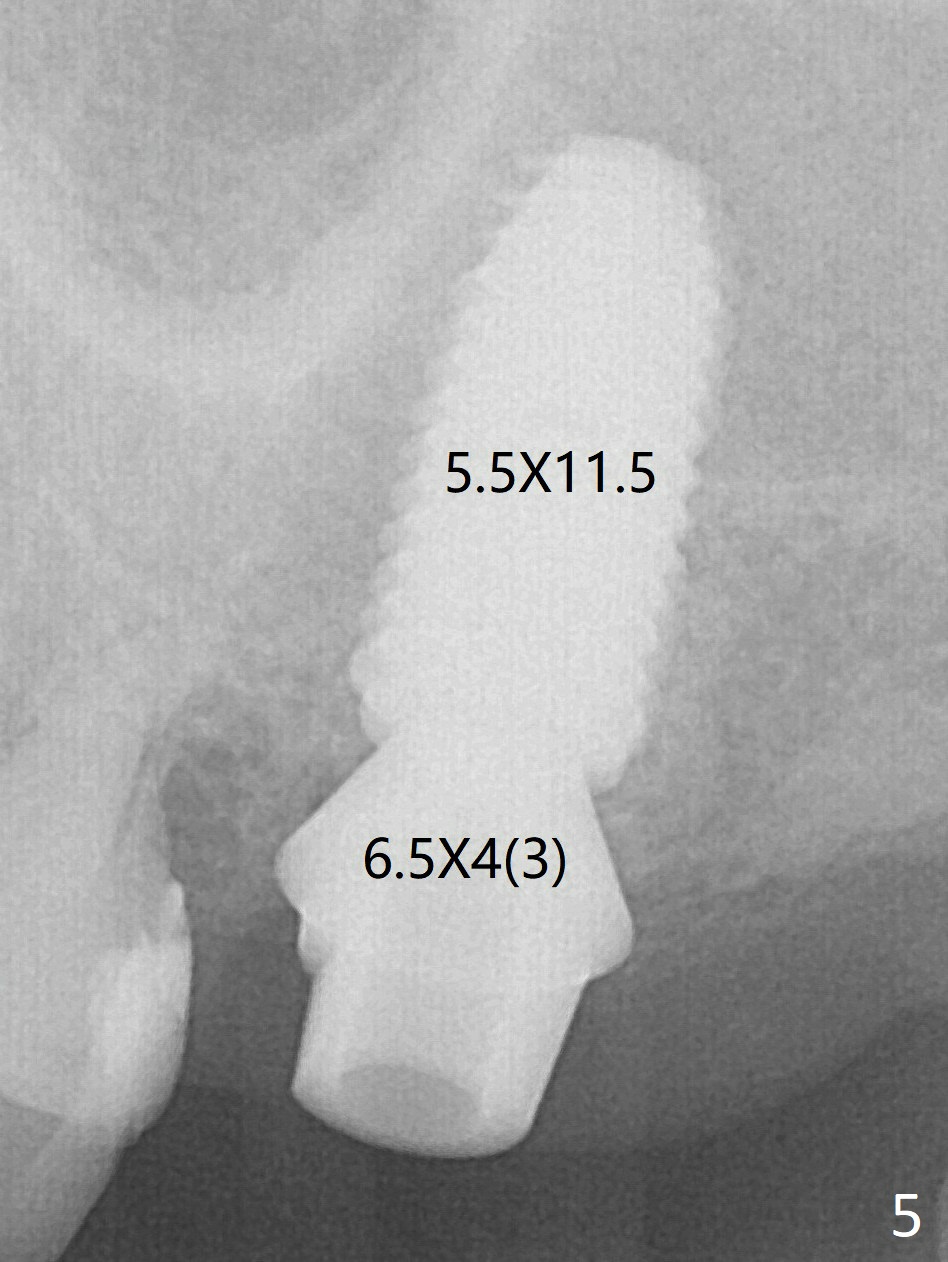

Although a 5x7.3 mm implant fits the site by design (Fig.4), a much longer implant is required to achieve primary stability past the sinus floor using IBS Magic Expanders (Fig.5,6 (20-30 Ncm)). In contrast, primary stability could not be obtained by engaging dummy implant to the socket walls. A short implant without sinus lift is associated with less obvious complication such as fibrointegration. The abutment will be rotated prior to impression. The implant seems osteointegrated 4.5 months postop (Fig.7). The abutment is changed to 6.5x4(5) mm before impression. There is no bone loss 5 months post cementation (Fig.8 (11 months postop)).